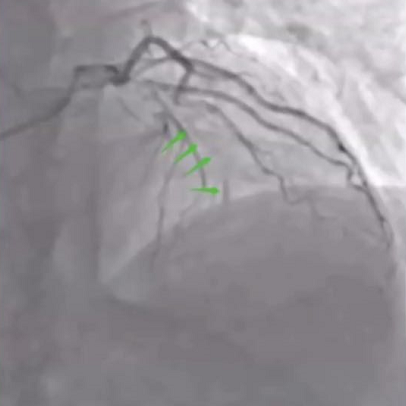

西安交通大学第一附属医院乌宇亮教授介绍到患者为一名67岁男性,主因“活动后胸闷气短1月、加重1周”入院,冠脉造影显示LAD及LCX近中段中重度狭窄,向RCA提供侧支循环;RCA异常开口于升主动脉,自近段闭塞,全程可见钙化影,CTO入口处有较大分支,出口处血管相对健康且粗大。

RCA自近段闭塞

RCA植入支架后

对于这一病例,广东省人民医院杨峻青教授认为RCA异位开口导致强支持的Guiding难以到位。术者合理使用各种技术,配合合理的器械选择,很好完成手术。小尺寸的Firefighter™球囊通过性好,多次扩张后仍保持优越性能,帮助手术成功。